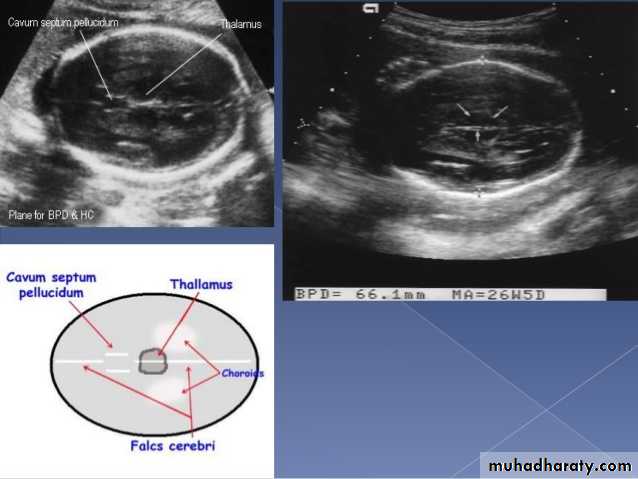

US of the obstetric & Gyne.BPD together with head circumference (HC), abdominal circumference (AC), and femur length (FL) are computed to produce an estimate of fetal weight. In the second trimester this may be extrapolated to an estimate of gestational age and an estimated due date (EDD) .

The BPD should be measured on an axial plane that traverses the thalami, and cavum septum pellucidum. The transducer must be perpendicular to the central axis of the head, and thus the hemispheres and calvaria should appear symmetric.